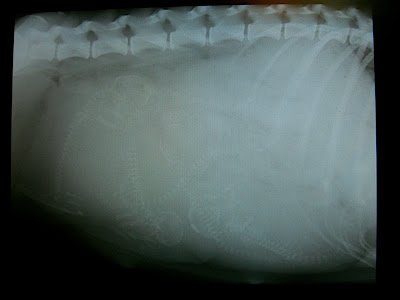

上面這張X光照片,顯示了一件我們最不想碰到的事

她懷孕了!!!!而且至少有五隻!!

醫生才驚覺,於是照了這張X光。

從X光照片看來,至少有五隻小狗狗在她的肚子裡!!